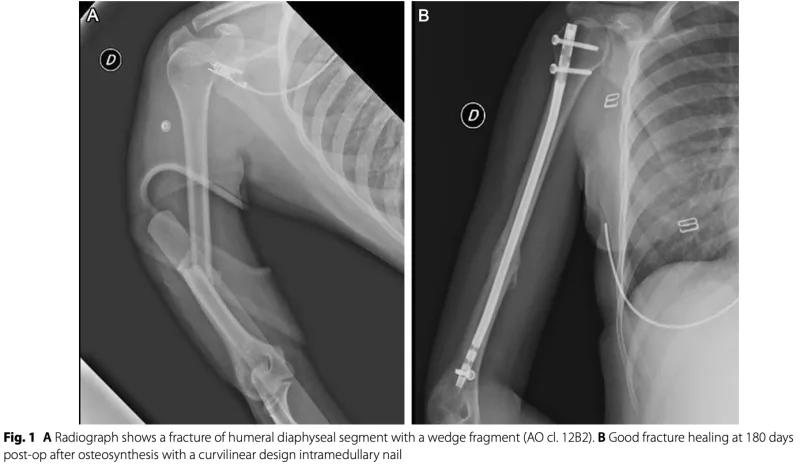

引き続き, 上腕骨骨幹部骨折の前期高齢者さんに対して, 上腕骨の中に髄内釘を挿入して固定する手術.

髄内釘が入ったところで, 多職種回診のため, 手術部を出ました.